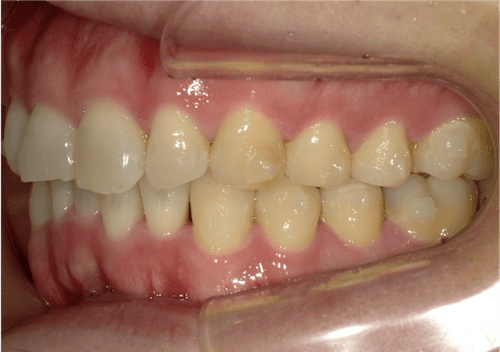

叢生(中等度)

BEFORE

AFTER

担当医コメント

上下の中等度の叢生がある。上顎の大臼歯の遠心移動が出来るスペースがある、補綴が多いのでIPRによってスペースが確保出来るのでインビザラインで治療を行った。

治療の概要

年齢/性別

26歳 女性

主訴

上下の歯並びが気になる。八重歯が気になるでした。

リスク

歯肉退縮が起こる可能性がある。叢生の改善により、ブラックトライアングルが出て来る可能性がある。

費用

85万円(矯正費用)

術前

術中

術後